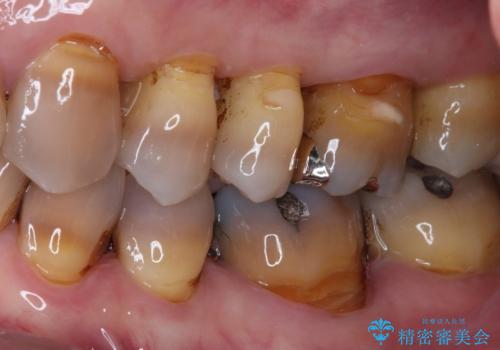

- 上顎大臼歯が食事の度に痛みを感じるとのことで来院された患者様です。

レントゲン写真などで診査を行ったところ、神経組織が壊死し、根尖部周辺の骨に炎症が認められました。

まずは根管治療を行い、症状が消退したことを確認してオールセラミッククラウンにて補綴治療を行うこととしました。